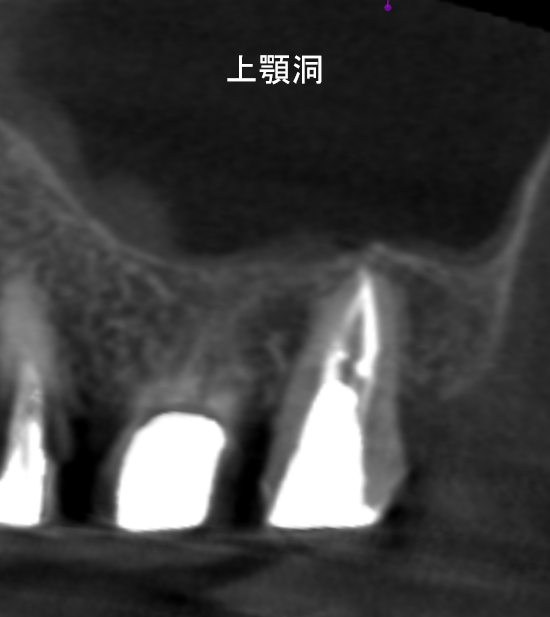

歯に穴が空いていて骨に炎症がある状態 |

CTでも歯の周囲に骨がないのが分かる。 |

| 医院の診断 | 虫歯の再発、歯性上顎洞炎を併発した慢性根尖性歯周炎 |

奥歯の虫歯が原因で蓄膿症になることがあります。患者様は昔から鼻炎があり耳鼻科通いでしたが、歯の治療により鼻炎が治りました。 |